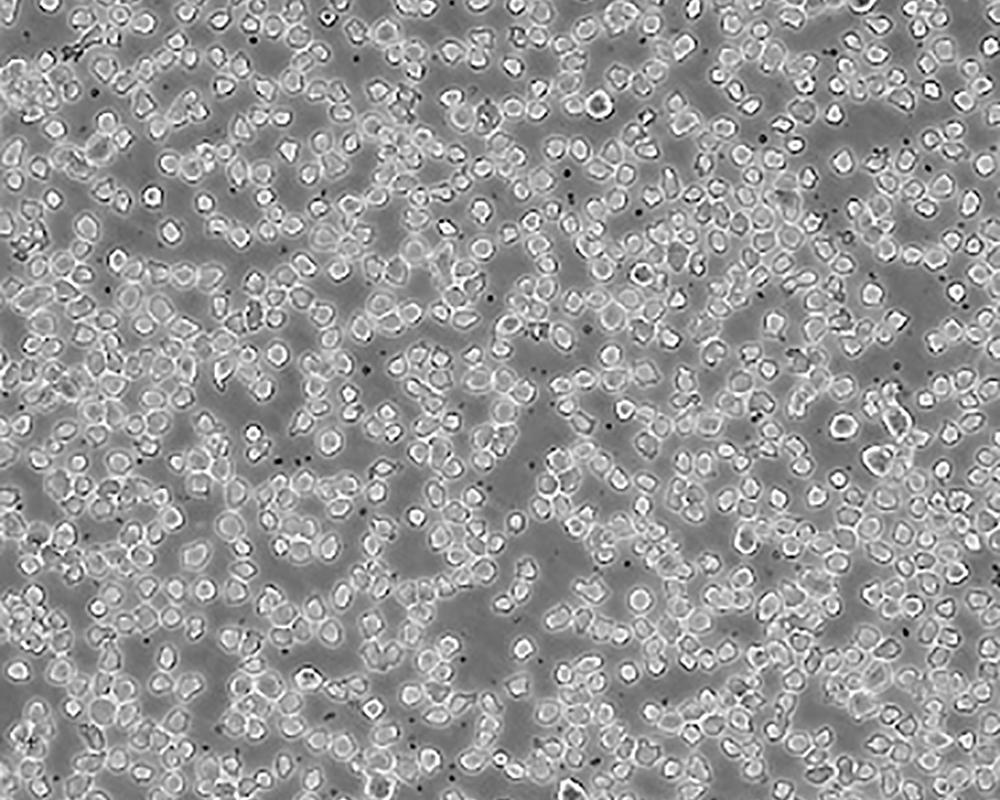

THP-1

產品名稱 THP-1

中文名稱 人單核細胞白血病

組織來源 急性單核細胞白血病;男性

生長特性 suspension

形態特征 monocyte

細胞描述 該細胞從一名1歲的患有急性單核細胞性白血病的男孩的外周血中分離建立。該細胞可以吞噬乳膠顆粒和激活的紅細胞,細胞膜和胞漿內均沒有免疫球蛋白,表達C3R和FcR;可受佛波酯TPA誘導向單核系方向分化;可作為轉染宿主。